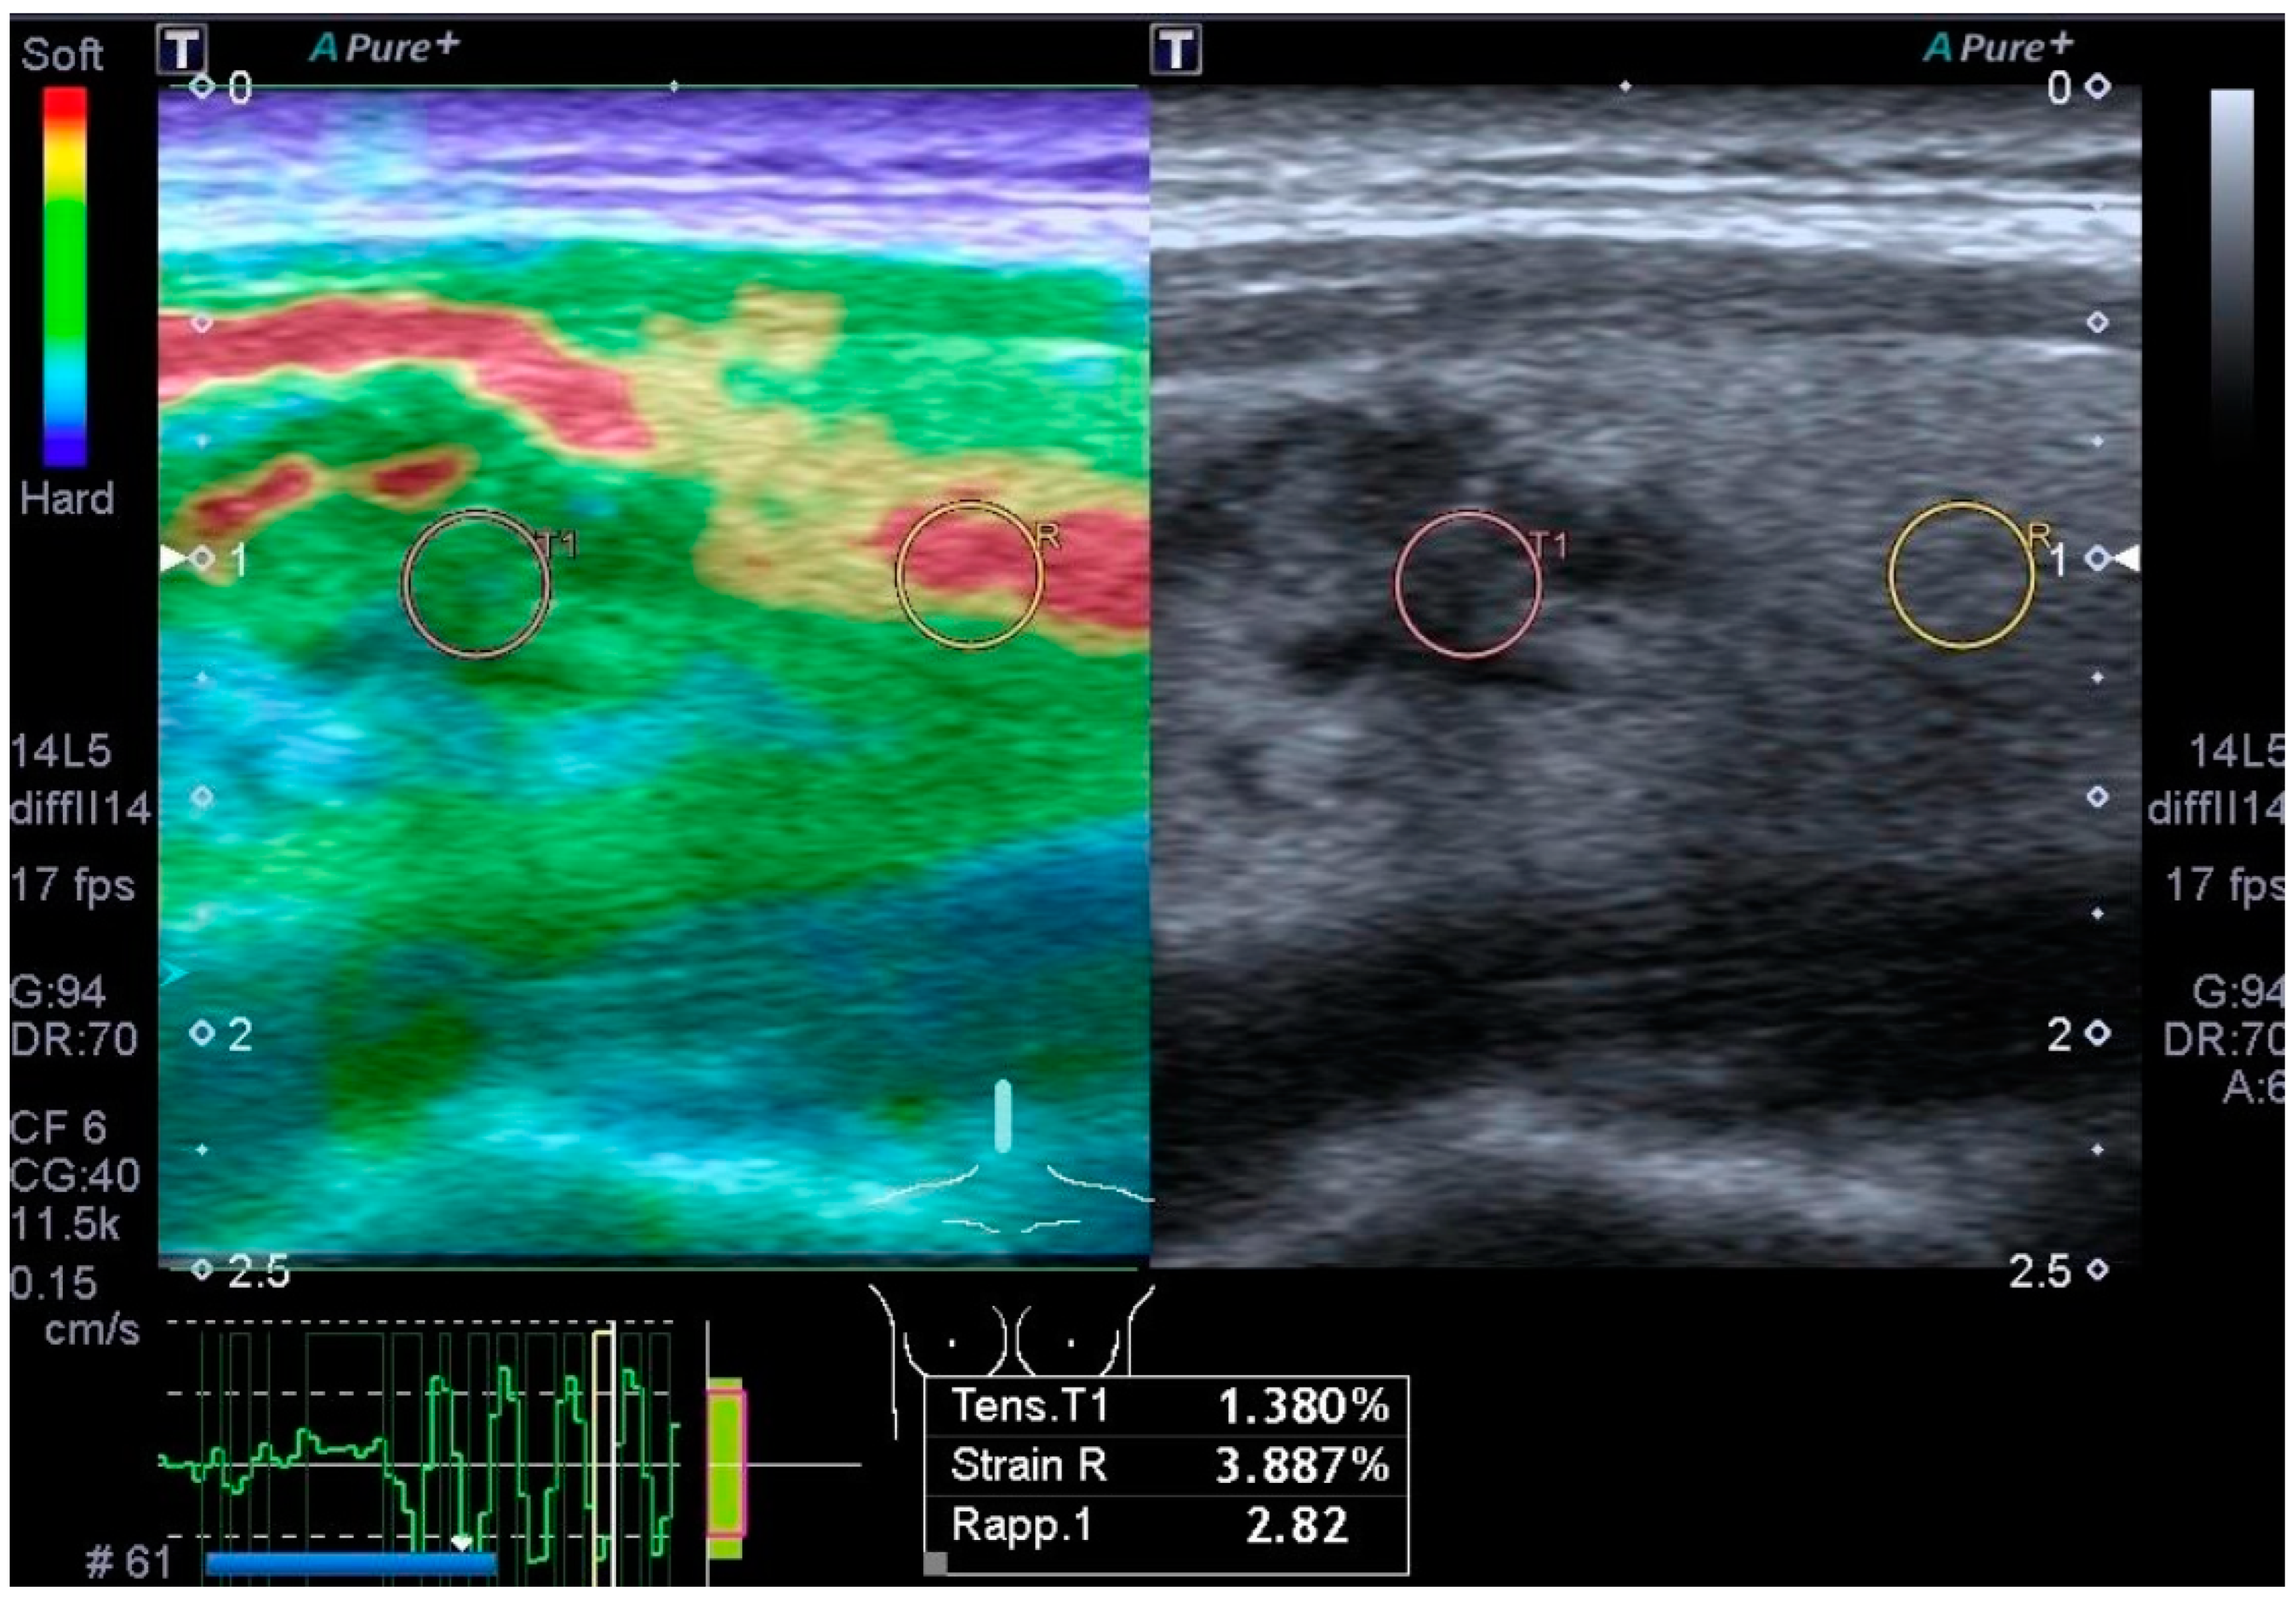

3.4. Elastography

- Cantisani, V.; Grazhdani, H.; Drakonaki, E.; D’Andrea, V.; Di Segni, M.; Kaleshi, E.; Calliada, F.; Catalano, C.; Redler, A.; Brunese, L.; et al. Strain US Elastography for the Characterization of Thyroid Nodules: Advantages and Limitation. Int. J. Endocrinol. 2015, 2015, 908575. [Google Scholar] [CrossRef] [PubMed] [PubMed Central]

- Cantisani, V.; David, E.; Grazhdani, H.; Rubini, A.; Radzina, M.; Dietrich, C.F.; Durante, C.; Lamartina, L.; Grani, G.; Valeria, A.; et al. Prospective Evaluation of Semiquantitative Strain Ratio and Quantitative 2D Ultrasound Shear Wave Elastography (SWE) in Association with TIRADS Classification for Thyroid Nodule Characterization. Ultraschall Med. 2019, 40, 495–503. [Google Scholar] [CrossRef] [PubMed]

- Okasha, H.H.; Mansor, M.; Sheriba, N.; Assem, M.; Abdelfattah, Y.; Ashoush, O.A.; Rakha, M.; Abdelfattah, D.; El-Sawy, S.S.; Elshenoufy, M.; et al. Role of elastography strain ratio and TIRADS score in predicting malignant thyroid nodule. Arch. Endocrinol. Metab. 2021, 64, 735–742. [Google Scholar] [CrossRef] [PubMed] [PubMed Central]